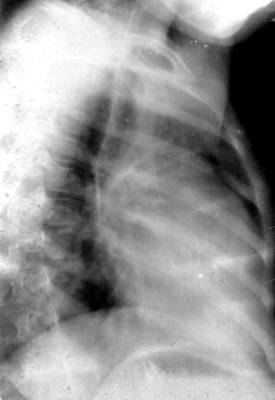

右心室增大影像学特征